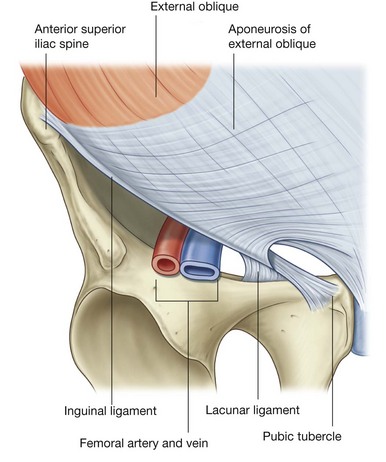

The lower border of the external oblique aponeurosis forms the inguinal ligament on each side (Fig. 4.27). This thickened reinforced free edge of the external oblique aponeurosis passes between the anterior superior iliac spine laterally and the pubic tubercle medially (Fig. 4.28). It folds under itself forming a trough, which plays an important role in the formation of the inguinal canal.

image

Fig. 4.28 Ligaments formed from the external oblique aponeurosis.

Several other ligaments are also formed from extensions of the fibers at the medial end of the inguinal ligament:

image the lacunar ligament is a crescent-shaped extension of fibers at the medial end of the inguinal ligament that pass backward to attach to the pecten pubis on the superior ramus of the pubic bone (Figs. 4.28 and 4.29);

image additional fibers extend from the lacunar ligament along the pecten pubis of the pelvic brim to form the pectineal (Cooper’s) ligament.

Fig. 4.29 Ligaments of the inguinal region.

The floor (inferior wall) of the inguinal canal is formed by the medial one-half of the inguinal ligament. This rolled-under, free margin of the lowest part of the aponeurosis of the external oblique forms a gutter or trough on which the contents of the inguinal canal are positioned. The lacunar ligament reinforces most of the medial part of the gutter.